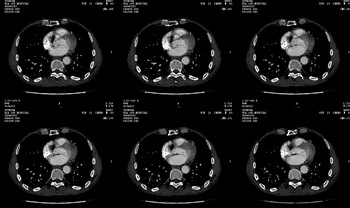

男 62 夜间突然腹痛并向背部放射 ,急诊疑胰腺炎 ,胰淀粉酶正常 ,ct示胰腺未见明显异常,发现降主动脉密度欠均,做主动脉造影示胸腹主动脉半月形低密度充盈缺损,内膜钙化并内移,累及腹腔干致根部明显狭窄,未见明显破裂口。 本人为是不典型夹层,其他人有说是动脉硬化或动脉炎的。请大家发表一下看法。

主动脉附壁血栓?主动脉夹层?

我觉得这个不像主动脉夹层,应该是血栓多点,如果可以重建个mpr也许对诊断更有帮助。